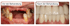

Echte Behandlungen aus unseren Excellence Centern

Vorher-Nachher-Vergleich des Mundes einer Person mit unregelmäßigen Zähnen und dann strahlend weißen, geraden Zähnen.

Vorher-Nachher-Vergleich des Mundes einer Person: links unvollständige Zähne, rechts vollständige, weiße Zähne.

Vorher-Nachher-Vergleich von Zähnen: links stark beschädigte Zähne und Zahnfleisch, rechts ein vollständiges Gebiss mit weißen Zähnen.

Zwei Bilder zeigen Zähne und Zahnfleisch: Vor der Behandlung mit beschädigten oberen Zähnen, nach der Behandlung mit gesunden, weißen Zähnen.